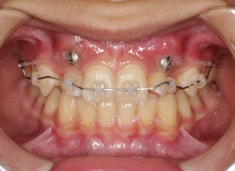

治療開始時

FX(フェイシャルアキシス)は85度なので東洋人の平均値に近く、下顎が前方に過剰成長するリスクは強くはありません。

しかしやはり上顎は劣成長で、下顎が優位な状態ではあります。

上下顎のギャップはありますが、顔面自体の幅径は良好な値を示していますので、スペース不足は拡大することによって解決できポテンシャルはあると考えられます。

左右の非対称もさほど強くありません。